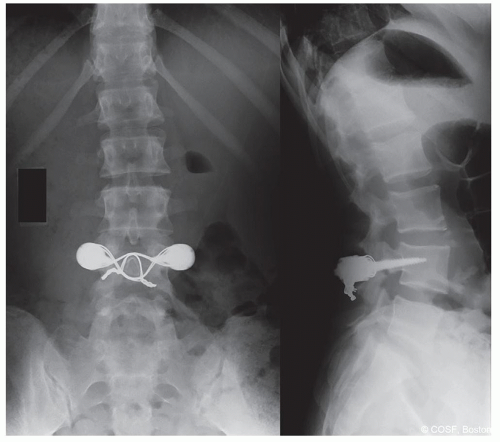

Spondylolysis/Spondylolistheses

M. Timothy Hresko

Pars Repair

Operative Indications

Failed nonoperative treatment of documented pars intra-articularis defect

MRI—absence of intervertebral disk degeneration

Less than 5 mm of translation of superior vertebral body

Pain relief on pars injection